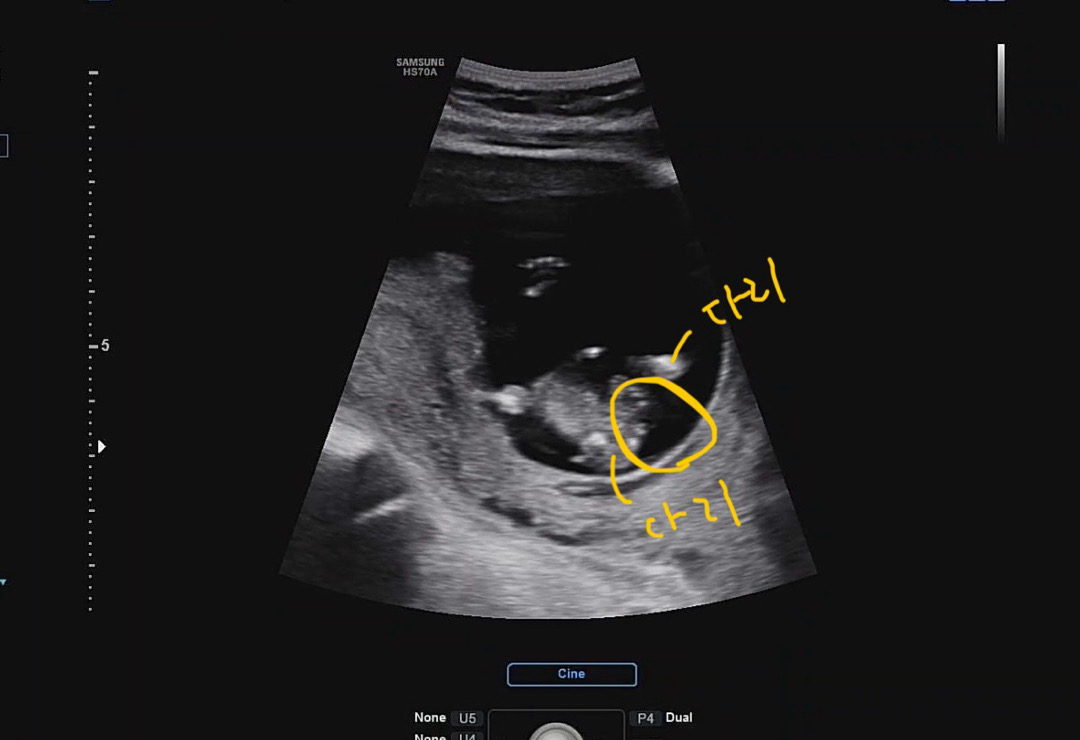

안녕하세요! 첫 글이라서 떨리네요☺️ 12주 지난 토요일에 보고온 초음파 사진 입니다. 아기 다리 사이 초음파인데, 성별이 궁금해요!!!

다리 사이 성별 봐주세요!